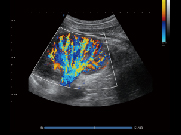

心脏,C模式

肾脏 C模式